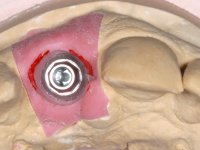

52-year-old female patient, non-smoker. He used an appointment with an implant already placed in the 1.1 site. It was provisionally rehabilitated with a composite resin crown adhered to the palatal surface of the adjacent teeth. This provisional had taken off several times in the last month, even in this first consultation it was taken off. We took advantage of this situation and verified that the “Tissue Level” implant had 2 to 3 mm of prosthetic space available. A deep bite and the inclination of the long axis of the implant posed a very difficult situation for the rehabilitator. If one chooses a abutment with a cemented crown, the height of the abutment would be minimal, with no retention or resistance. If a screwed solution is chosen, the screw access hole would emerge through the vestibular surface. It should be remembered that in 2006 the prosthetic solutions for this situation were limited to these options: 1- Screw-retained angled metal abutment for cemented crown 2 - Screw-retained angled metal abutment for transversally screw-retained crown 3 – Syn Octa metal abutment for screw-retained crown. A serious problem in this rehabilitation was guessed right from the start. The patient had a thick gingival phenotype and good oral hygiene.

After the impression of the implant using a double-mix technique with double viscosity and the collection of shape and color information by the ceramist, we proceed with the work. In the model, a syn octa was placed over the implant, and a screw was placed on it to assess its emergence in relation to the incisal edge. Then, an adequate emergence profile in the artificial gingiva was prepared. A abutment with characteristics suitable for overbite and simultaneously capable of receiving a veneer was waxed on top of this scenario. This waxing gave rise to the manual milling of a very personalized abutment. An infrastructure in Zr was also made for the veneer with a very great adaptation to the abutment. On this infrastructure ceramics were placed. Ceramic fluorescence sought to compensate for the lack of fluorescence that Zr had and obviously further customize the aesthetics. The adhesive bridge was removed and the definitive work was placed. The syn octa was initially tightened with 35 N to the implant and then the Zr abutment was tightened over the syn octa with 15 N. The access hole was plugged and then the veneer was cemented with resin-reinforced glass ionomer. After 15 years, the patient returned to the consultation with tooth mobility. Fortunately, nowadays we have the possibility of having dynamic tightening wrenches that allow tightening screws with greater inclinations. An access cavity was made without damaging the incisal edge of the veneer. Tightening was done with a dynamic wrench with 15 N torque. The hole was covered with Teflon and filled with composite resin. This solution allowed the problem to be solved in a simple and economical way.